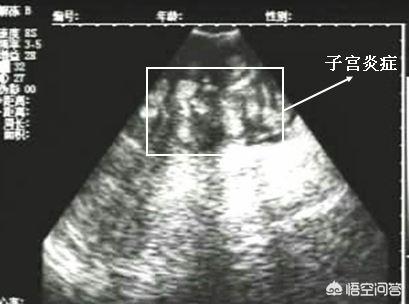

2.有实验证明,母猪产后可以在子宫吸收内毒素,